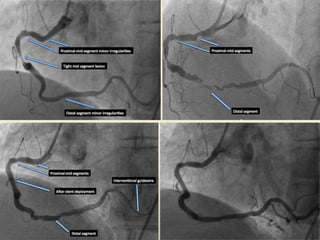

Optimum guide wirepositioning • Should be placed as distally as possible in the target vessel • Allows extra support when crossing with balloon/stent catheters • ↓ chance of the wire becoming displaced backwards across the lesion and necessitating re-crossing Avoid vessel perforation when positioning wires with hydrophilic coatings very distally